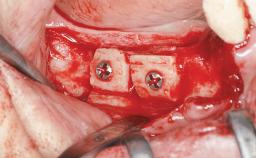

Bone Augmentation Horizontal|Simultaneous|Sinus Floor Elevation|Staged

Augmentation Materials Xenogenous|Membrane

Bone Volume Deficient vertically or deficient vertically AND horizontally